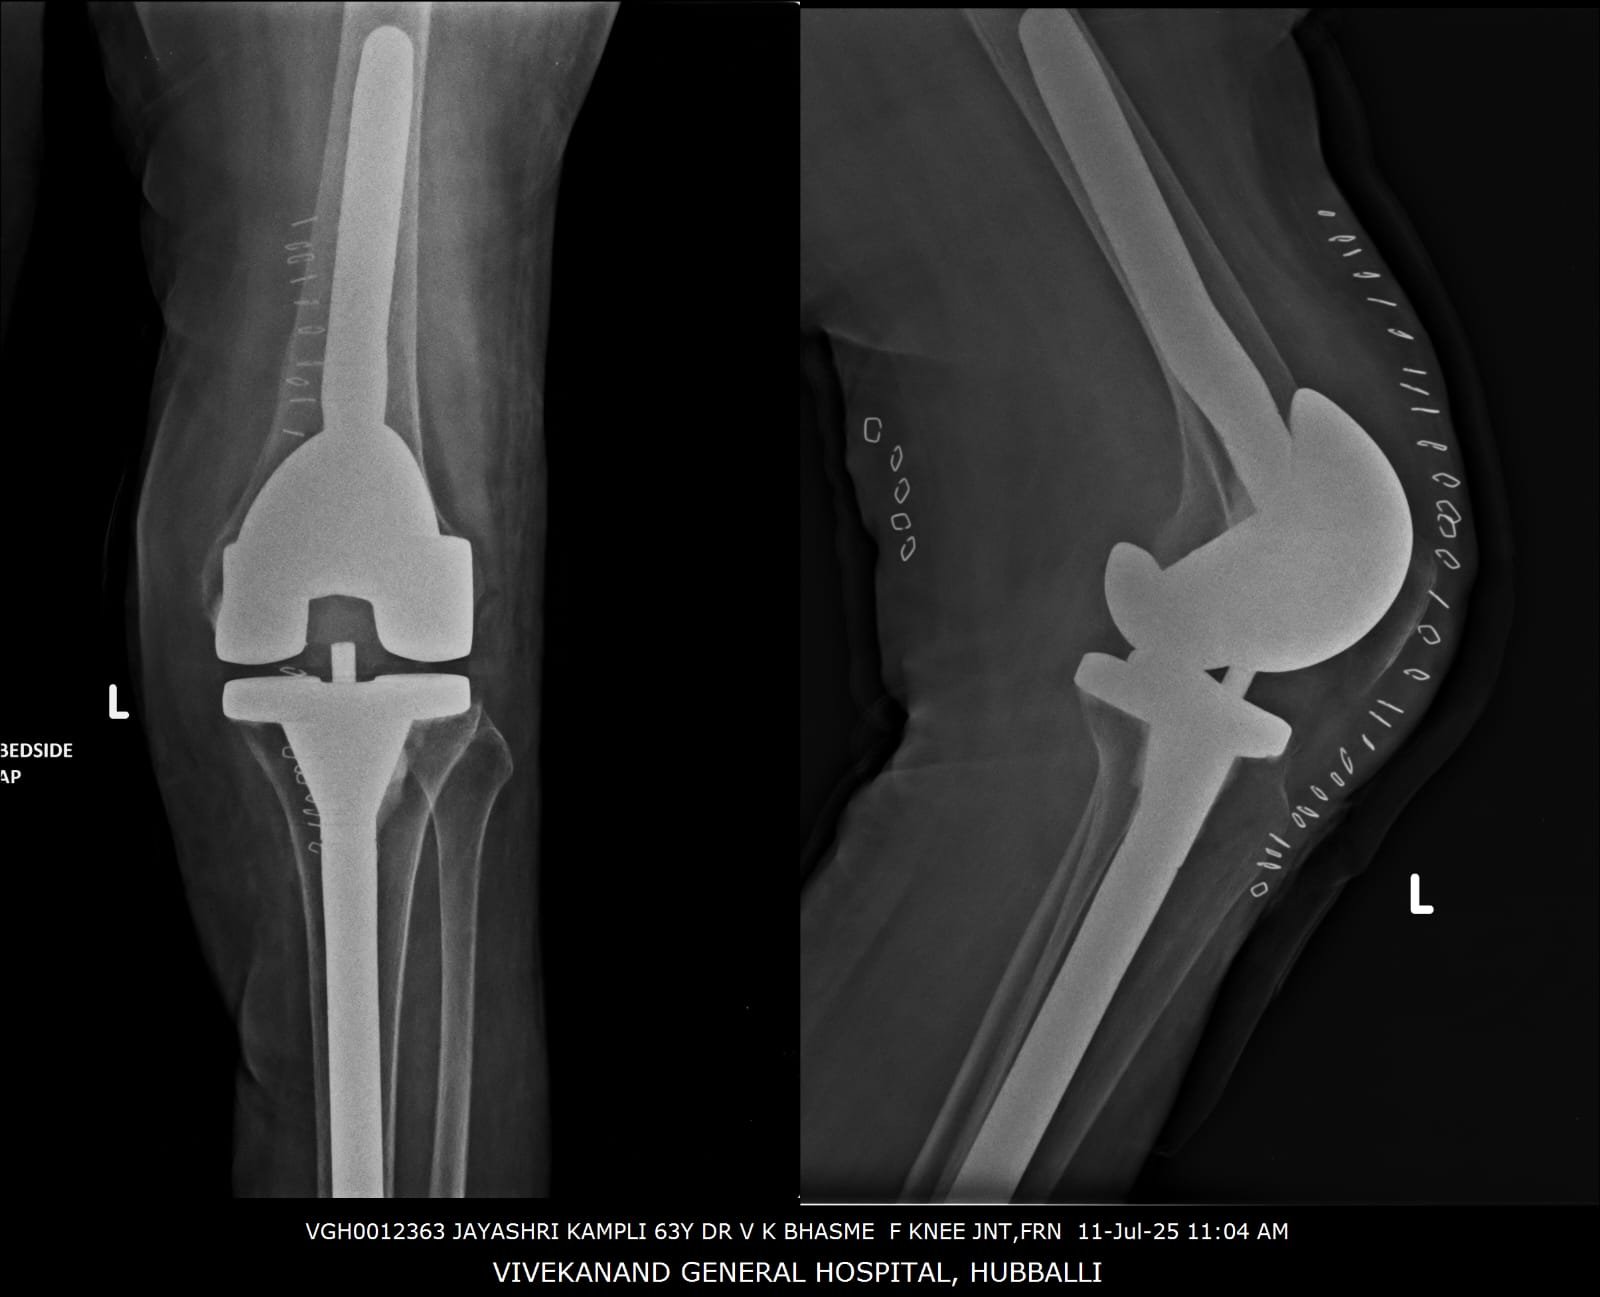

68 years lady was not walking for 5 years 8 months